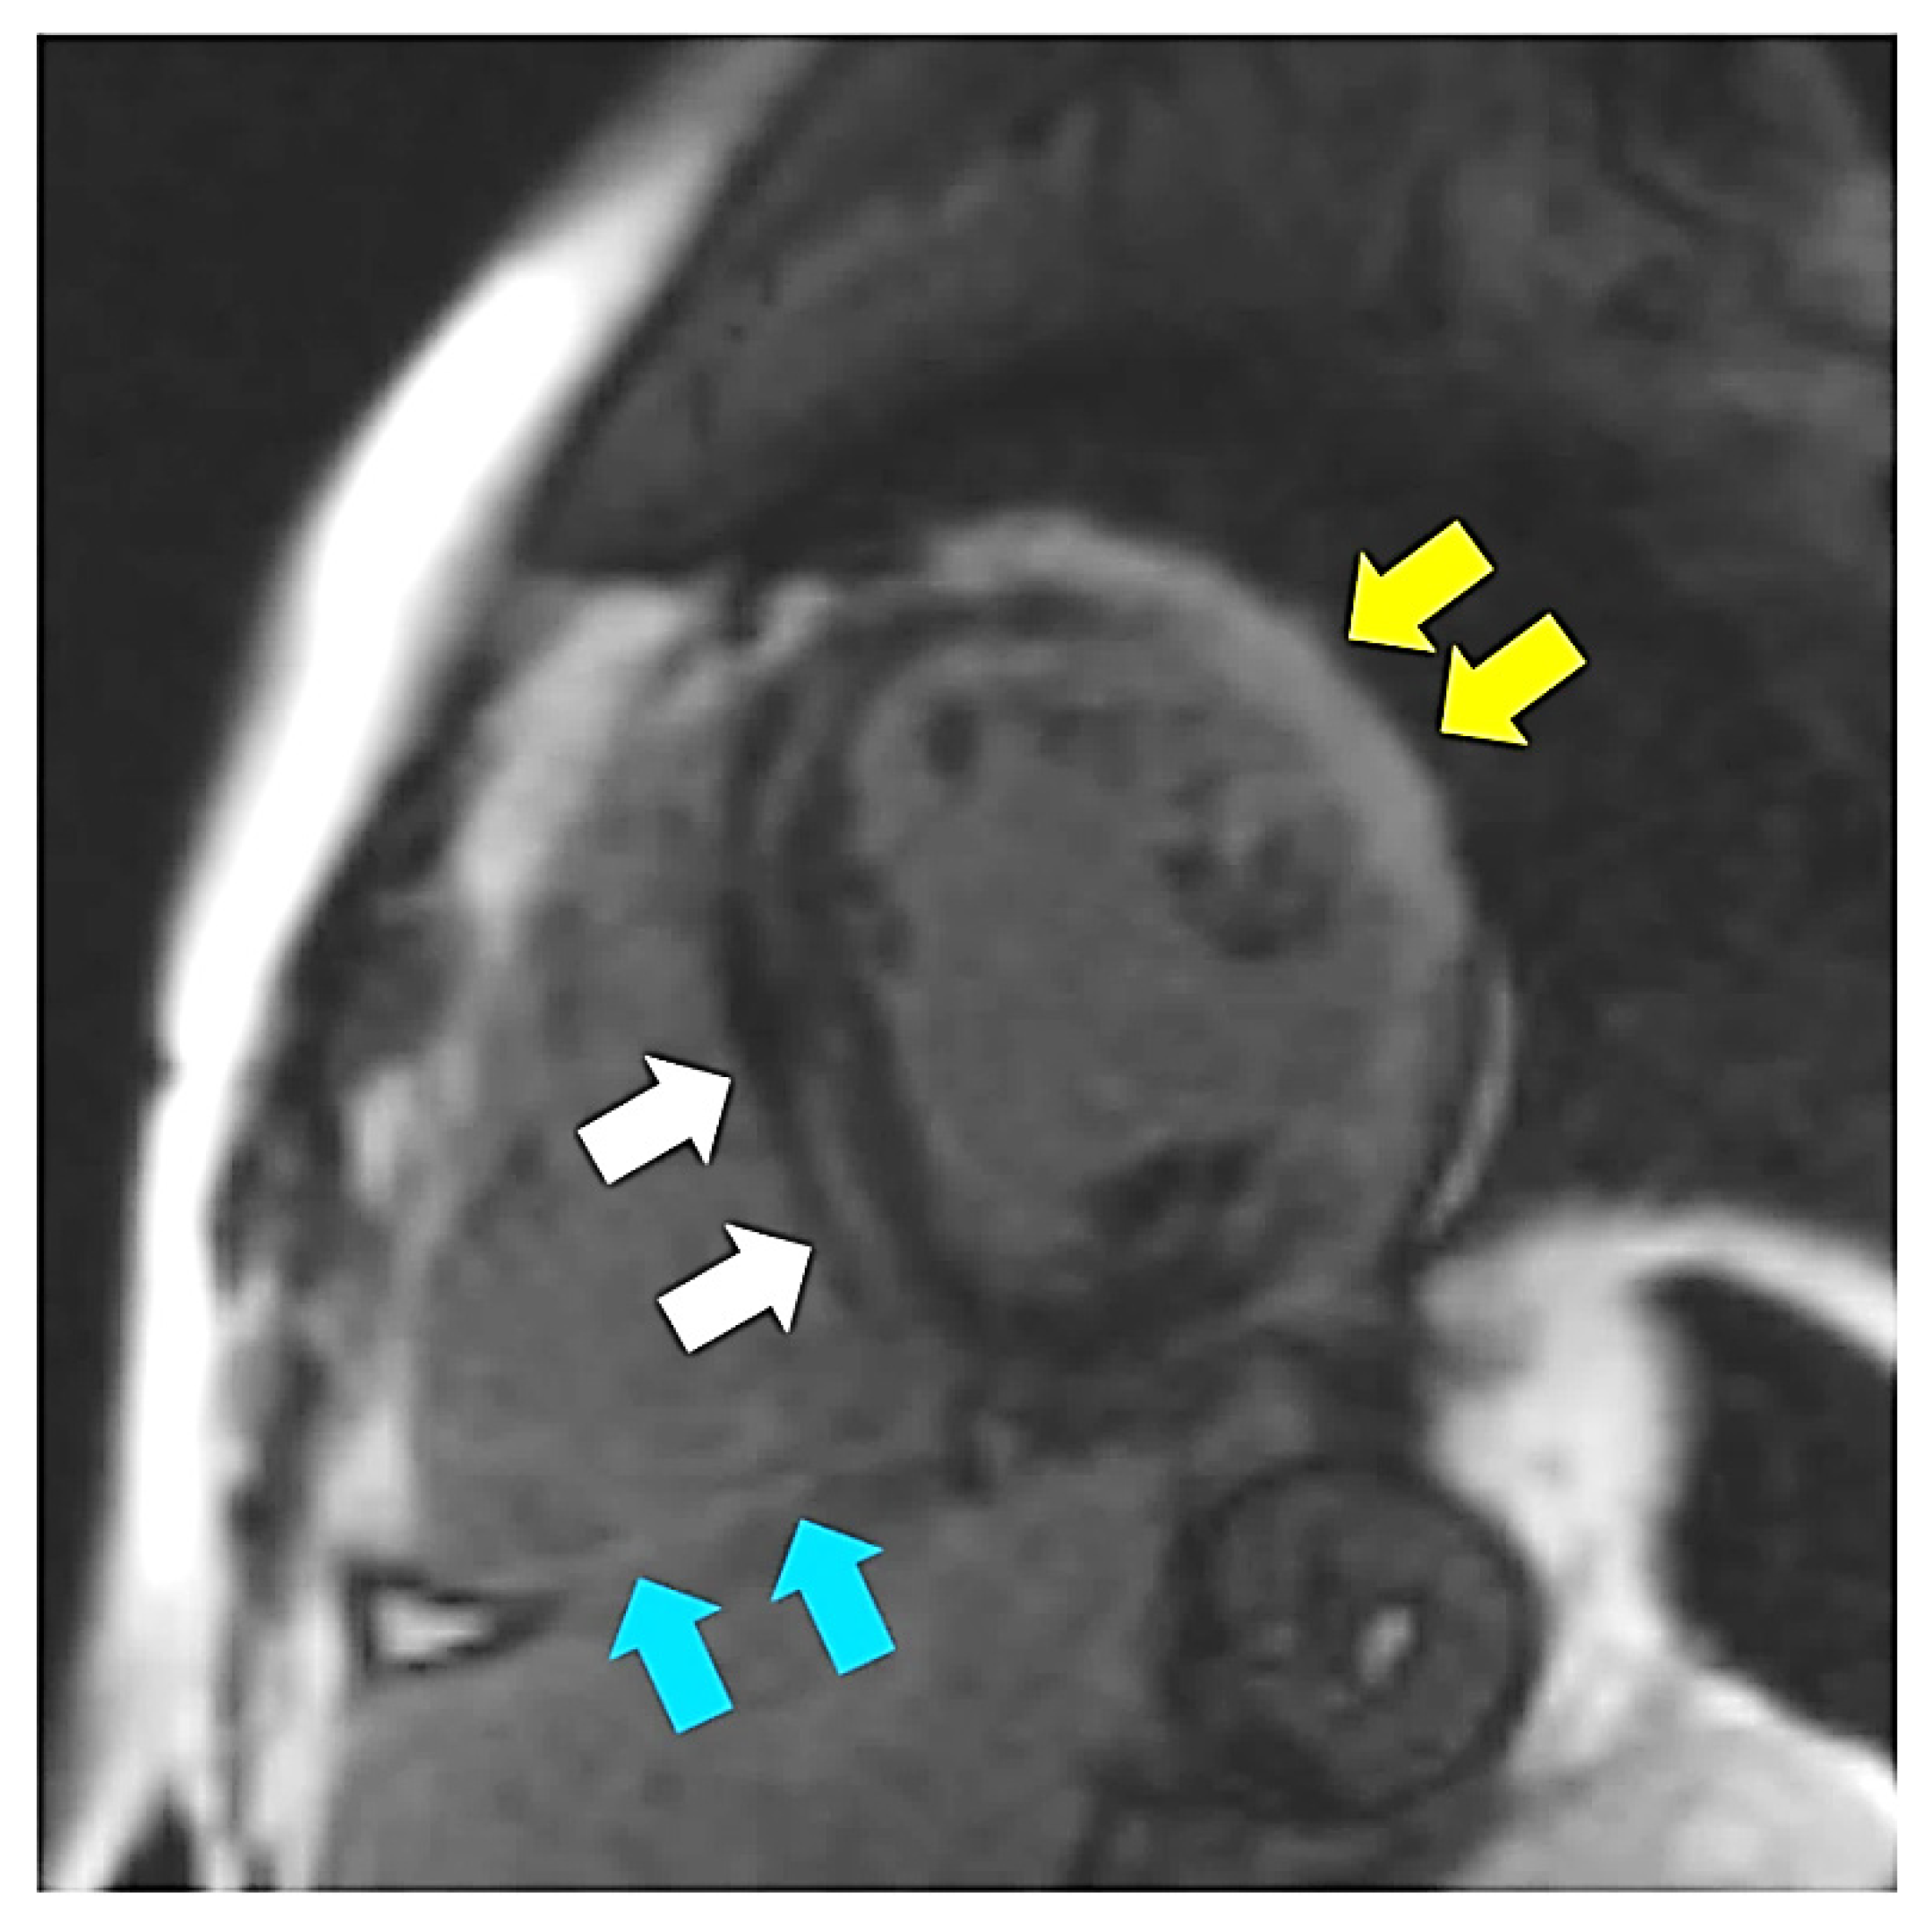

Figure 5.

Late gadolinium enhancement short axis image demonstrating midwall fibrosis in the interventricular septum (white arrows) as well as transmural fibrosis in the left ventricular lateral wall (yellow arrows) and in the inferior wall of the right ventricle (blue arrows).